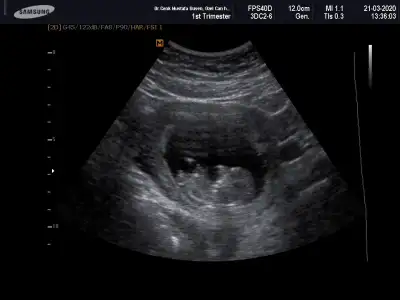

Merhaba yeni uyeyim elimde 7 haftalik karindan 10 haftalik alltan ulturason goruntusu var cinsiyet tahmini yapabilirmisiniz acaba şimdiden teşekkurler ilk resim 7 hafta karin son resim 10 haftta altan bakildi.

Keseye göre erkek ama tutmayabilir siz 11 12 13 haftaları paylaşın

Banada bakarmısınız şimdi ikili testten çıktım doktor erken dedi soylemedi çok merak ediyorum 12 haftalik